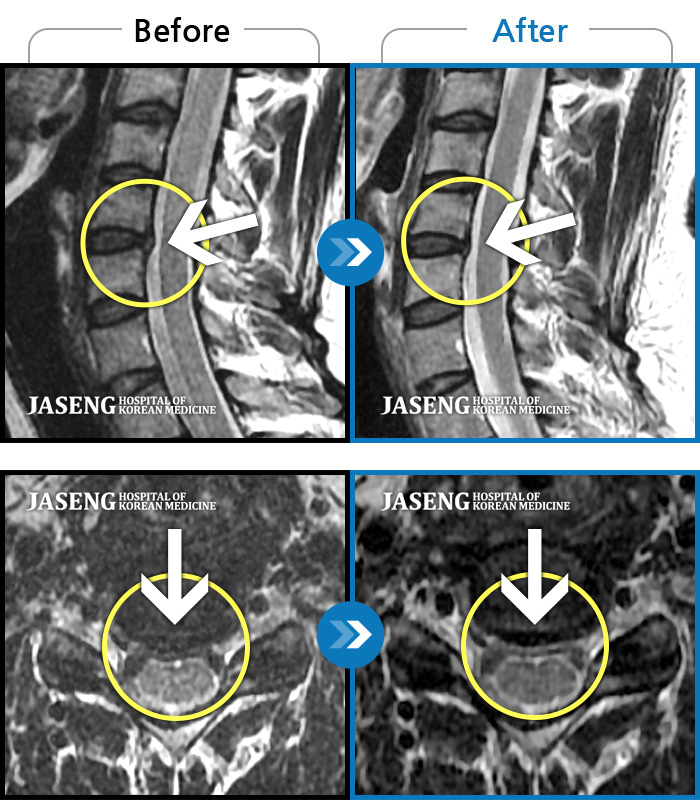

ȯںп Ǹ ǿ ԿǾ, ο ġ ۿ Ƿ ġḦ Ͻñ ٶϴ.